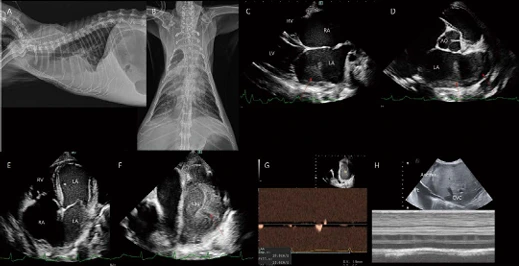

Unknown age, 암컷, 4.1kg, DSH 환자가 심한 구내염, 유연, 호흡 곤란 증상으로 응급 내원하였습니다. 흉부방사선 검사에서 cardiomegaly, pulmonary congestion이 관찰됩니다. 흉부방사선 외측상에서 cranioventral lung field와 accessory lung field에서 patchy한 폐침윤 소견이 관찰됩니다(A). 복배상에서 양쪽 후엽 특히 우측 후엽과 accessory lung field에서도 patchy한 폐침윤 소견이 관찰됩니다(C). 폐초음파 검사에서 B profile(diffuse confluent B lines with lung sliding) with thin even pleural line이 관찰됩니다(B). 심초음파 검사에서 HCM(hypertrophic cardiomyopathy phenotype)이 관찰되어, 이로 인한 좌심부전, 심원성 폐부종 상태로 임상적 가진단 하였습니다. 응급중환자실(ECC, emergency and critical care)에서 이뇨제를 포함한 심장약, 산소 등의 supportive care를 진행하였고, 다음날 바로 폐부종이 개선되어 퇴원하였습니다(D, E). 이 환자는 HCM에 준한 치료 모니터링을 받았으며, 초진 1년 4개월 후 심한 심원성 폐부종이 반복되고, 상태가 위중하여 보호자님이 안락사를 결정하셨습니다.

여기서 잠깐 비교증례!

< HCM with pulmonary edema >

image.png?type=w966

4살 중성화 암컷 5.7kg DSH 환자가 목욕 후 호흡 곤란으로 내원하였습니다. 흉부방사선 검사에서 cardiomegaly가 관찰됩니다. 그러나 pulmonary congestion은 관찰되지 않습니다. 오히려 흉부방사선 외측상에서, 심음영 전방에서 폐전엽으로 가는 폐혈관들이 얇게 관찰됩니다. Pulmonary hypoperfusion 상태로 고려됩니다. 폐야 전반에 걸쳐 faint interstitial and alveolar infiltration이 관찰됩니다. 특히 양쪽 후엽의 침윤 밀도는 center에서 periphery로 갈수록 감소되는 양상을 보입니다. 폐초음파에서 폐야 전반에 걸쳐 B profile (diffuse confluent B lines without lung sliding) with irregular thickened pleural line이 관찰됩니다. 심초음파에서 Hypertrophic phenotype의 feline cardiomyopathy 상태가 확인됩니다.

그러나, 흉부방사선 검사에서 고양이 심장병으로 인한 일반적인 심원성 폐부종(patchy alveolar infiltration in the cranioventral and accessory lung field) 양상을 보이지 않고, 오히려 pulmonary hypoperfusion 상태로 생각되며, 또한 폐초음파에서 confluent B line이 관찰된다고 하더라도 lung sliding이 소실되고, pleural line irregularities가 관찰되므로 목욕물 오염으로 인한 비심원성 폐부종(noncardiogenic pulmonary edema, NCPE) 상태가 고려됩니다. 이 환자는 응급중환자실에서 일시적 이뇨제 trial, 산소 및 supportive care에 반응이 없고, 점점 악화되어 사망하였습니다.

고양이 심원성 폐부종은 개와 달리, 흉부방사선 검사에서 심음영의 전방으로 cranioventral lung field와 심음영 후방으로 accessory lung field에 침윤 밀도가 patchy하게 관찰되는 경향이 있습니다. 그리고 심원성 폐부종은 심비대와 함께 pulmonary congestion 소견이 동반되나, 비심원성 폐부종은 pulmonary congestion이 관찰되지 않거나, hypoperfusion 상태를 보일 수 있습니다. 폐초음파에서 extravascular lung water는 B line으로 나타나게 됩니다. 심원성 폐부종과 비심원성 폐부종의 폐초음파 소견은 매우 유사합니다. 그러나 미세한 차이로 lung sliding, pleural line irregularities, B line homogeneity, concurrent pulmonary consolidation 정도가 다를 수 있습니다. 심원성 폐부종은 빠르게 발생하고 적절한 치료를 통해 빠르게 개선될 수 있는데, 이는 vascular endothelium가 아직 스스로 빠르게 회복할 수 있기 때문입니다. 따라서 normal lung sliding, thin and even pleural line, homogeneous B lines을 보이는 경향이 있습니다. 비심원성 폐부종은 폐 모세혈관 압력 상승보다는 심각한 전신적 요인으로 인해 단백질, 염증 세포 및 체액이 폐포에 축적되며, 폐포 상태가 한번 손상되면 치유되는데 훨씬 더 오랜 시간이 걸리게 됩니다.

따라서 폐초음파에서 lung sliding이 소실되는 B' profile, thick and uneven pleural line, inhomogeneous B lines 등이 관찰될 수 있습니다. 더 나아가 비가역적 수준의 ARDS(acute respiratory distress syndrome)로 진행된다면 심한 consolidation이 동반되기도 합니다. 비심원성 폐부종은 초기 손상 후 일반적으로 24~48시간 또는 그 후에 좀 더 심각해지고, 약 5일 후 안정화되며 완전히 회복되는 데 몇 주가 걸릴 수 있다고 알려져 있습니다. 응급 내원 당일뿐만 아니라, 입원 치료 기간 동안 적어도 24시간 간격으로 2번 이상 폐초음파를 보게 되면 환자의 현상태 및 진행 여부를 판단하고, 치료 방향 및 예후를 제시할 수 있습니다.